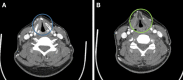

Improving Safety in Chondrolaryngoplasty